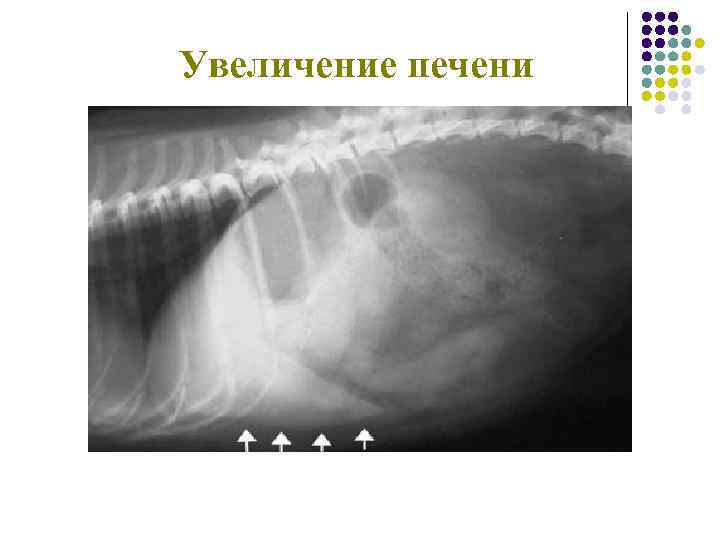

Печень Увеличение

Гепатомегалия

Увеличение печени Жировая дистрофия печени у кота при сахарном диабете.